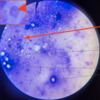

Trypanosoma equiperdum: Trypomastigotes

Trypomastigote in the blood